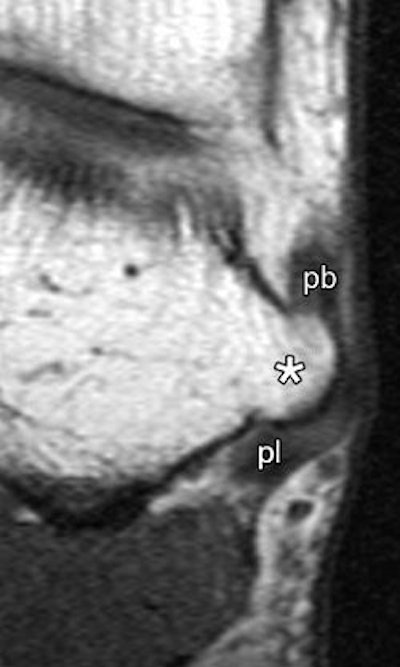

| Enlarged peroneal tubercle. T1-weighted MR images in (above) transverse oblique (45° between coronal and transverse planes, 572/14) and (below) coronal (572/14) planes show enlarged peroneal tubercle (*) in 60-year-old male asymptomatic volunteer. pb = peroneus brevis tendon, pl = peroneus longus tendon. |

| Figure 3ab, Saupe N, Mengiardi B, Pfirmann C, Vienne P, et al. "Anatomic Variants Associated with Peroneal Tendon Disorders: MR Imaging Findings in Volunteers with Asymptomatic Ankles". Radiology 2007; 242(2): 509-517. |

"The median size of the peroneal tubercles was 2.6 mm on transverse oblique T1-weighted images and 2.9 mm on transverse T2-weighted images," the authors wrote. "The mean angle between the plantar fascia and the longitudinal axis of the tibia was 98˚" (Radiology, February 2007, Vol. 242:2, pp. 509-517).

- The term "enlarged peroneal tubercule" and "enlarged retrotrochlear eminence" should only apply to structures of more than 5 mm.